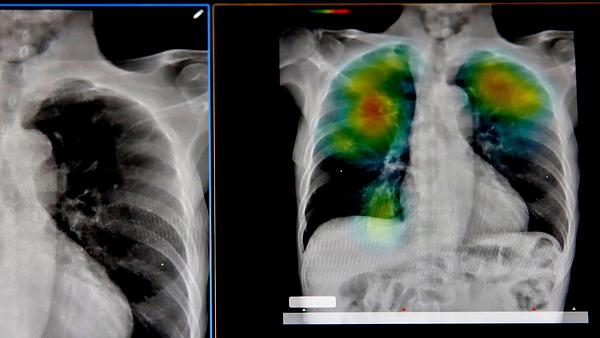

AI-alapú korAI diagnózis: beteg leszel, mielőtt betegnek érzed magad?

Egy kínai kutatócsoport az Intelligent Medicine szerkesztőségi írásában azt javasolja, hogy az orvoslás a tünetek utáni hajsza helyett a tünetek előtti időablakra álljon rá: AI-modellek folyamatosan figyelnék a gének, fehérjék és kémiai jelzések hálózatainak időbeni változásait, és a közelgő instabilitás mintázatait keresnék. A megközelítés a dinamikus hálózati biomarker elmélethez igazodik, amely szerint a szervezet betegség felé közeledve bizonyos molekuláris hálózatok erősebben ingadoznak és szokottnál összekapcsoltabbá válnak. Influenza-vizsgálatokban ezek a mintázatok már napokkal a tünetek előtt kirajzolódtak, daganatok esetében pedig hasonló jelek jelentek meg azon a ponton, amikor a sejtek rosszindulatúvá kezdenek válni. A közölt példák szerint az ilyen előrejelzések pontossága 80 százalék feletti tartományban mozog. A mostani diagnosztikai gyakorlat sokszor populációs átlagokra támaszkodik; az újabb AI-módszerek ezzel szemben egyéni mintázatokra hangolnák a megfigyelést. Gyakorlati alkalmazásban ez személyre szabott monitorozást jelentene: például 1-es típusú diabétesznél digitális egyéni szimulációkkal a vércukor-alakulás a korábbiaknál jóval pontosabban lenne modellezhető. Hasonló elvet lehetne szívizom-elégtelenség és más kórképek követésére is bevetni. A koncepció azonban adatéhes: folyamatos, tiszta mérési adatok nélkül – vagy nagy hiányok mellett – a rendszer téves riasztásokat adhat, látszat-összefüggéseket találhat. További gond a „feketedoboz”-jelleg és az AI-hallucinációk kockázata: a modell olyan predikciót is kiadhat, amelynek belső okát még a fejlesztők sem tudják megmagyarázni. A kép tehát nem a „Doctors May Soon Be Able” típusú helyettesítésről szól: az AI legfeljebb korai figyelmeztető rendszer lehet, amely kockázatokat jelez a tünetek előtt. A végső értelmezés és döntés továbbra is szakorvosi feladat marad – ők mondják ki, hogy az „Diagnose Illnesses Before You Ever” jellegű előrejelzés valóban „Feel Sick As” indokolt-e, vagy csak félrevezető összekapcsolás.